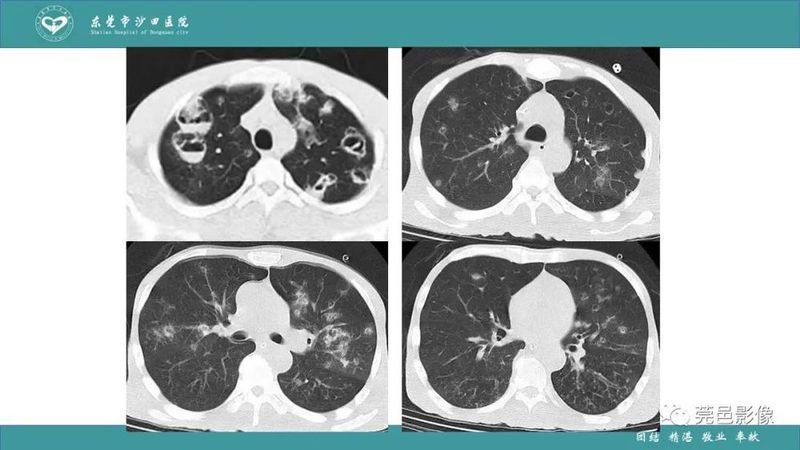

「肺炎克雷伯杆菌肺炎」影像学诊断+鉴别诊断